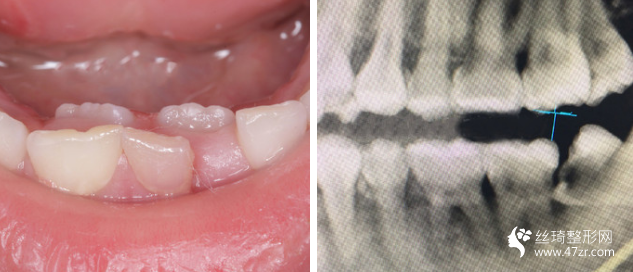

我的牙齒其實問題不大,但是下面兩個牙齒被擠的歪了出來,而且我 一直覺得我的嘴有點往外凸出,所以一直都有矯正的想法,朋友在他 們家做的貼面,推薦給我說薇琳醫(yī)生很專業(yè)的,所以我也就過來了。 首先做了檢測,然后設(shè)計了方案,取模,然后根據(jù)自己的牙齒情況制 定矯正器。 耐心等待我矯正器的到來。